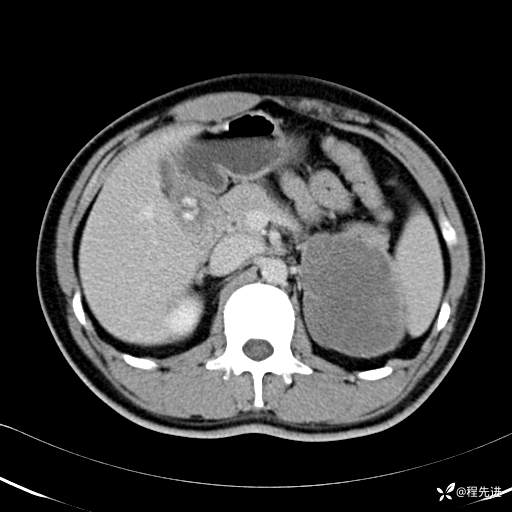

【腹盆】特别精彩病例|体检发现的左侧腹膜后占位期待您的精彩解读

患者年龄:25岁

简要病史:体检发现

CT平扫:(CT值:平扫,27HU,动脉期,27HU,门静脉期,31HU,平衡期,32HU)

平衡期: